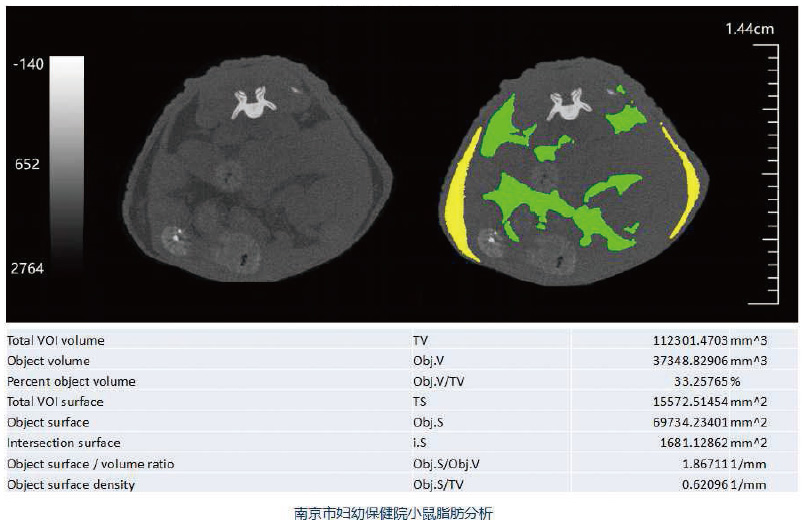

Hiscan VM Pro是一款快速灵活的活体显微CT,主要用于动物实验。其所用的锥束X射线可以看到样本的内部结构,最高分辨率可达18μm。可做小动物全身扫描,如小鼠、大鼠等。同时,可以扫描所选择的感兴趣区域,例如小鼠和大鼠的头部、脊椎、前肢 、后肢等。根据样本尺寸不同配以不同尺寸的扫描床,独特设计的扫描床可以防止小动物逃逸落进机器内。

广泛应用于骨骼疾病、肿瘤疾病、心血管疾病、炎症疾病、代谢疾病、免疫学、药效评价、生物材料等学科的临床前研究。